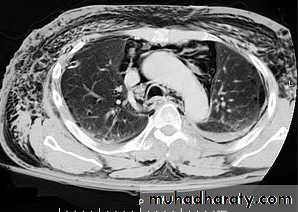

• A mediastinal mass due to a hiatus hernia is usually easy to diagnose on plain films because it often contains air and may have a fluid level, best seen on the lateral view

Large hiatus hernia, seen with fluid in stomach

Right Pericardial fat pad

Rt. Cardiophrenic pericardial cyst

Morgagni, retrosternal, diaphragmatic hernia